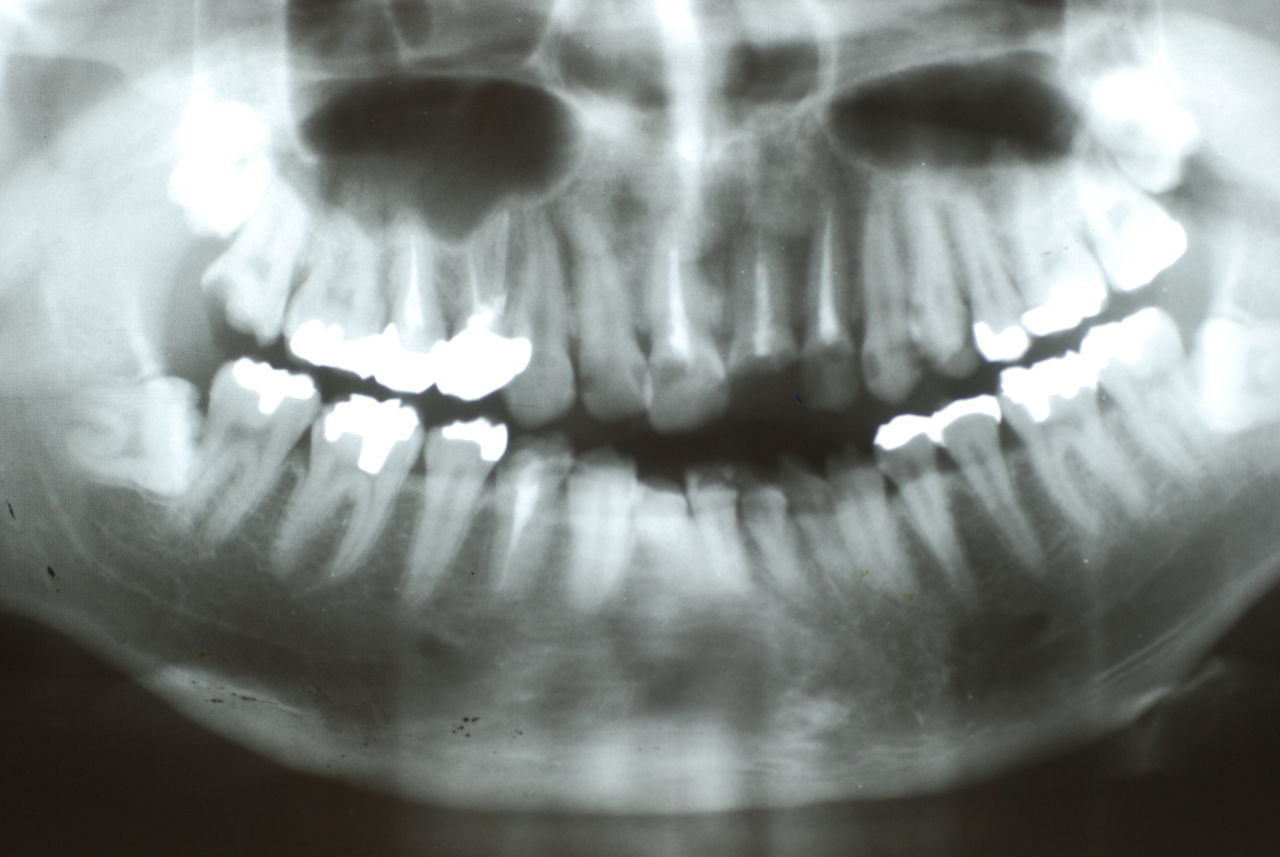

下の写真の方は虫歯と歯の間の歯周病が酷かったのです。

虫歯の治療も完全にできませんし、歯の位置が悪く又重なっている為に歯周病が治らずに説得に数カ月を有した後に矯正することになりました。